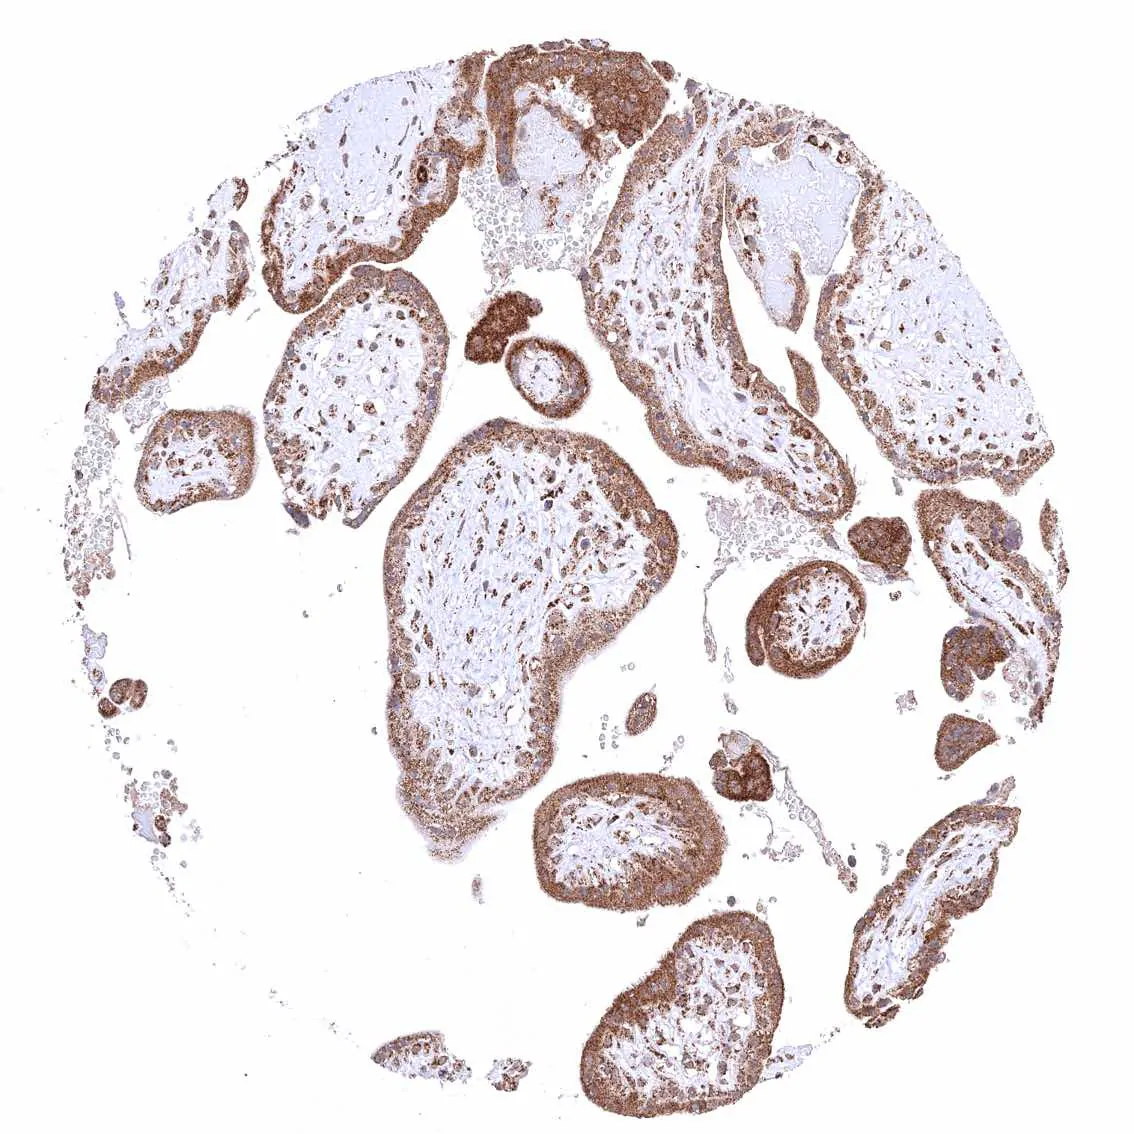

Placenta (amnion and chorion) – Distinct cytoplasmic ATP5J staining of amnion and chorion cells.